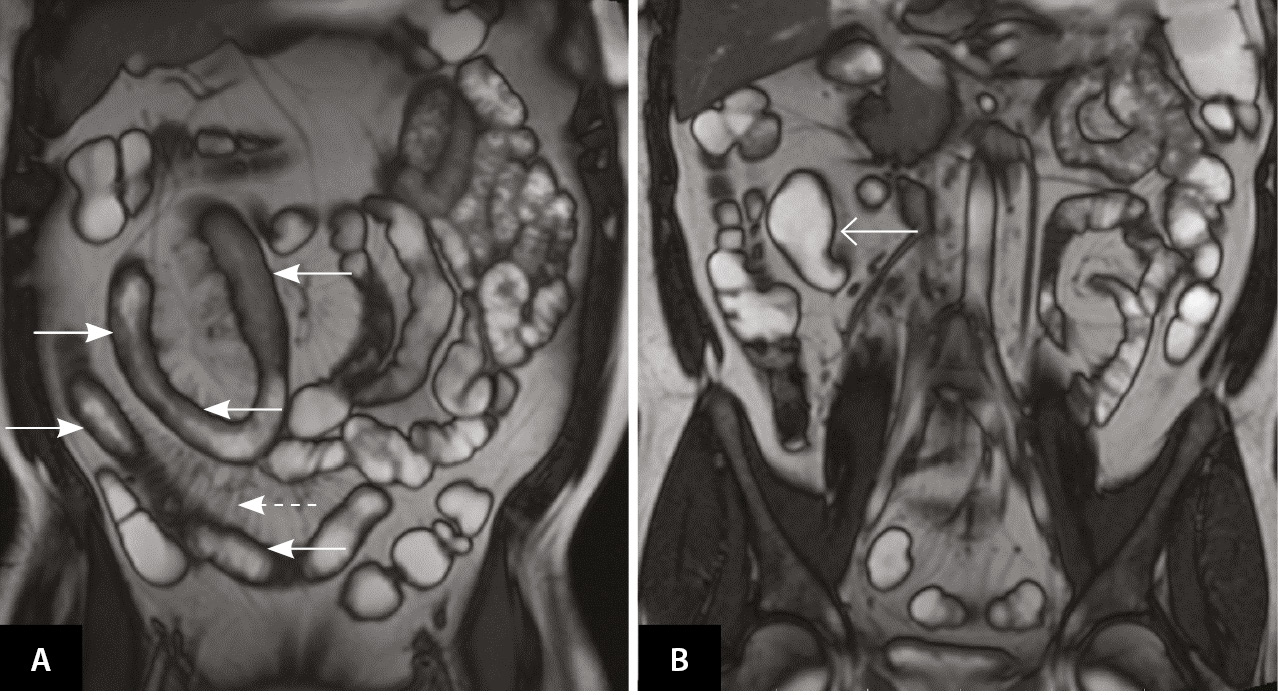

В начале февраля 2021 г. терапия адалимумабом была отменена, 17.02.2021 инициирована терапия канакинумабом 150 мг 1 раз в 4 недели подкожно и снижена доза колхицина до 1,5 мг в сутки. На этом фоне пациент отметил полное прекращение атак ССЛ. После отмены адалимумаба через несколько месяцев стали рецидивировать эпизоды динамической кишечной непроходимости. Пациент отказывался от проведения хирургического лечения и в течение последующих 2 лет продолжал наблюдаться у гастроэнтеролога. Периодически на фоне болевого синдрома в анализах отмечалось повышение СРБ. Получал курсами метронидазол, преднизолон внутривенно, с временным положительным эффектом. Продолжалась также терапия канакинумабом 1 раз в 4 недели с полным контролем атак ССЛ. В апреле 2022 г. выполнена энтероскопия, выявлены единичные эрозии проксимального отдела подвздошной кишки, множественные язвы терминального отдела подвздошной кишки, стриктура илеоцекального клапана (рис. 2). Пациент согласился на оперативное вмешательство.

Рис. 2. Энтероскопия от 08.04.2022: множественные сливающиеся эрозии и язвы под фибрином (сплошная стрелка), участки гиперемии слизистой оболочки в терминальном отделе подвздошной кишки (пунктирные стрелки)